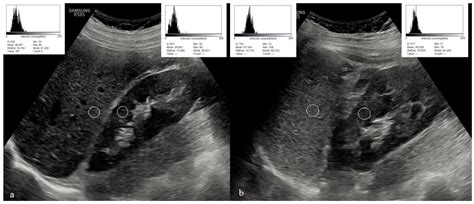

Radiologists categorize the liver's appearance into three primary grades based on how the echoes are reflected. Recognizing these variations is the first step in identifying underlying liver disease:

• Hyperechoic Liver: This occurs when the liver appears brighter than the kidney. It is the most common indicator of hepatic steatosis, or fatty liver disease, where fat cells infiltrate the liver tissue.

• Hypoechoic Liver: This happens when the liver appears darker than normal. This can occur in cases of acute hepatitis, where inflammation causes cellular swelling, or occasionally in specific types of infiltrative diseases.

• Non-Alcoholic Fatty Liver Disease (NAFLD): The accumulation of excess fat causes the liver to reflect more ultrasound waves, leading to increased echogenicity.

• Liver Cirrhosis: As the liver develops scar tissue (fibrosis), the architecture becomes coarse and irregular, often appearing brighter than a healthy liver.

• Hepatitis: Viral or autoimmune inflammation can change the cellular texture, sometimes resulting in a darker, "starry sky" appearance.